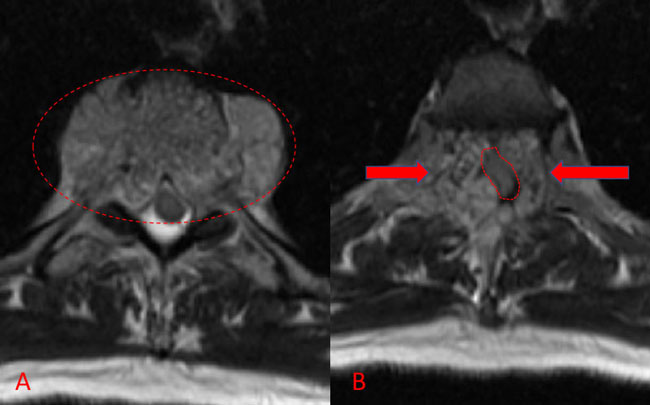

Spinal angiography showed a very hypervascular lesion fed predominantly by the right supreme intercostal artery (Figure 2. A, B).

Figure 2. (A, B) Selective angiography of the right supreme intercostal artery demonstrates extensive hypervascularity of this aggressive T3 hemangioma.

No spinal artery contributions were found to arise from this right T1-T3 pedicle. Superselective WADA testing was performed with Brevital injected through the microcatheter, which failed to elicit changes in the intraoperative monitoring, confirming safety to proceed with devascularization of this pedicle and tumor. This was performed with 100-300 micron particles achieving an excellent devascularization (Figure 3. A, B).